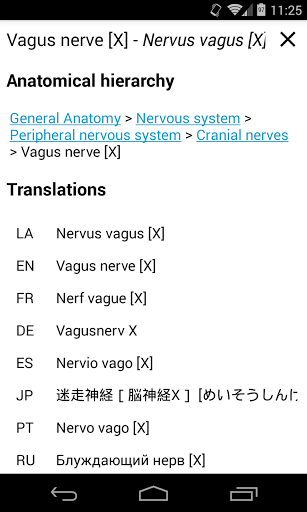

* تصفح بين الأجزاء التشريحية باستخدام روابط الوصف

- يتم الآن عرض المصطلحات المتعلقة بالهيكل التشريحي في عرض التفاصيل - تمت إضافة